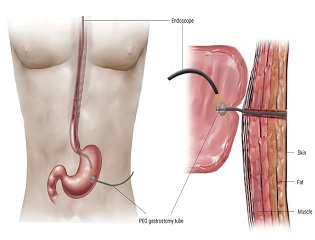

❈ What is a PEG?

A percutaneous endoscopic gastrostomy (PEG) is a procedure for placing a feeding tube directly into the stomach through a small incision in the abdominal wall with the assistance of an instrument known as an endoscope. The procedure is performed as a means of providing nutrition to patients who cannot take food by mouth. Many stroke patients, for example, have poor control over their swallowing muscles and are unable to safely consume enough food, or they have muscle weakness that allows food to leak into the lungs when they swallow things by mouth. Many of these patients will benefit from a PEG tube in order to receive adequate nutrition and to prevent them from respiratory problems that develop when food or fluids accidentally gets into the lungs.

❈ What are the medical indications for a PEG?

A PEG should be considered for pediatric and adult patients who are unable to consume sufficient food by mouth to meet their daily needs. These patients should be able to digest and absorb their food once it arrives in the stomach. The most common medical conditions requiring a PEG feeding tube are neurologic conditions associated with poor swallowing, such as experienced by stroke patients, and patients with cancers of the oral cavity or esophagus that prevent them from swallowing.

Other diseases of the esophagus that decrease a patient’s ability to swallow are also common indications for placing a PEG feeding tube. Patients with Alzheimer’s disease often lose their ability to swallow near the end of their life expectancy. The benefit of PEG tube placement in this patient group remains controversial. When a patient is being considered for PEG tube placement, the patient’s life expectancy and quality of life after the tube is placed should be considered to determine if placement of a feeding tube is appropriate.

❈ What is the medical procedure for placing a PEG tube?

PEG tubes are placed with the aid of an endoscope, an instrument to see inside your stomach and intestines. The patient receives sedatives and pain medications to make them comfortable. After confirming proper location and preparing the abdominal wall, a small incision is made in the abdomen. The PEG feeding tube is placed though this incision into the stomach. The procedure takes 15 to 20 minutes.

❈ Is there discomfort after the procedure?

There will be some minimal discomfort after the procedure from either cramping from gas in the digestive system or pain at the incision site itself. This pain can be well controlled with pain medication if required.

❈ Will the tube fall out once it is placed?

The tube is prevented from coming out of the stomach by one of several methods. Some commercial PEG brands have a mushroom-shaped cap on the end of the feeding tube inside the stomach. This cap is 2-3 times the diameter of the feeding tube. This cap is also called the internal bolster or internal bumper. Other systems employ a balloon at the end of the tube which is inflated once the tube is inserted, serving the same purpose. These internal bolsters prevent the PEG feeding tube from falling out.

❈ What does the PEG tube look like on the outside after placement?

The PEG tube has a diameter size about the same as a writing pen. Approximately 6 to 12 inches of tubing will protrude from the incision area. There will be a disc or a tubular device placed around the feeding tube lying against the abdominal wall. This is known as the external bolster or external bumper. It is meant to keep the tube from migrating forward into the stomach. At the outside end of the feeding tube is a capped plug. It may be a one hole or two hole plug. The plug is meant to be closed to prevent stomach content from getting on the skin and clothes of the patient. It is opened to allow food, medications and water to be placed through the PEG feeding tube. Suctioning of air and stomach contents can also be performed.

❈ What are the complications of a PEG tube?

Complications from this procedure may occur. Minor complications include leakage of food or fluid around the tube onto the abdominal wall surface, pain at the incision site, mild bleeding at the incision site or infection at the incision site. You should consult with your doctor if this occurs. Major complications are rare but can occur and include major bleeding, peritonitis (an infection inside the abdominal cavity) and damage to the colon or other surrounding organs. Delayed complications include “buried bumper” syndrome in which the internal bolster buries itself into the stomach wall. This can be avoided by not tightening the bolster too tightly.

❈ Are there alternatives to PEG?

There are alternatives to PEG feeding tubes. Nasogastric (NG) feeding tubes are tubes passed through the nose into the stomach for feeding. It is secured to the face with tape. Long-term use of these tubes can cause irritation, infection or bleeding of the nose and throat. These tubes also have a tendency to be accidentally pulled out. Also, a surgeon can place a feeding tube into the stomach in the operating room or a radiologist can place a feeding tube into the stomach in the fluoroscopy (X-Ray) suite. Similar procedures can be done to place feeding tubes into the jejunum as well, depending on the clinical scenario.

❈ How do you take care of a PEG tube?

The area around the incision on the abdominal wall should be cleaned daily and the incision may be covered with clean gauze. Often, these gauze sponges have a slit in them so they can be placed around the PEG tube, over the incision. The tube itself has centimeter markings written on the side. The centimeter marking at or near the incision site should be noted. If this number changes, the tube should be readjusted back to the original centimeter marking. The external bolster should rest gently near the abdominal wall. This external bolster should not be placed too tightly against the abdominal wall or it may lead to infection or skin ulceration.

Should the tube accidentally come out, it must be replaced within twenty-four hours or the incision may begin to close and new PEG procedure may be required. If the tube falls out, a physician should be contacted as soon as possible. A urinary (Foley) catheter can be temporarily inserted into the track to keep it open until a standard PEG tube can be replaced. If the tube needs removal or replacement, it is usually wise to wait 6 or more weeks after insertion before removal.